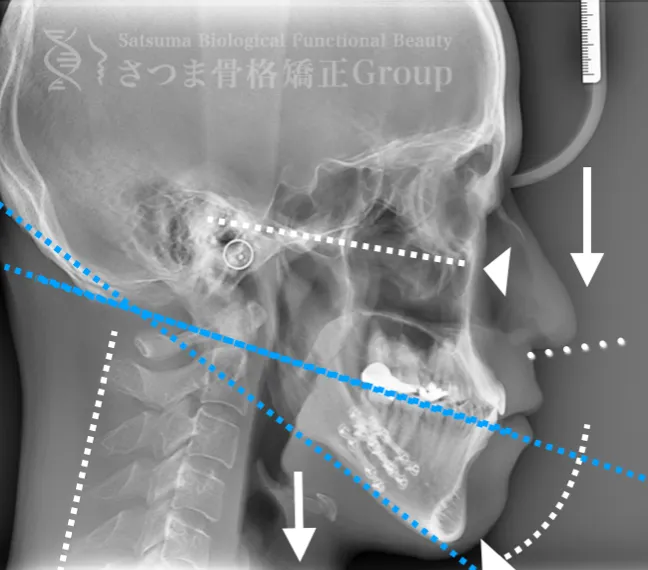

渋谷TMJ歯科クリニックでは、頭蓋および頸椎の歪みが顎位(あごの位置)と咬合(噛み合わせ)の乱れを引き起こし、その結果として顔の歪み、顎関節症、食いしばり、ストレートネックによる強い肩こり、さらには自律神経の乱れへとつながると考えています。

これらの問題を正確に評価するため、当院では セファロシステムによるレントゲン撮影(X-ray images) を行っています。

セファロ撮影によって 顎関節・頭蓋骨・頸椎の位置関係を客観的に可視化でき、施術前の状態を科学的に把握することが可能となります。

施術の前後で撮影したレントゲン写真を比較することで、改善の度合いや変化を一目で確認できます。